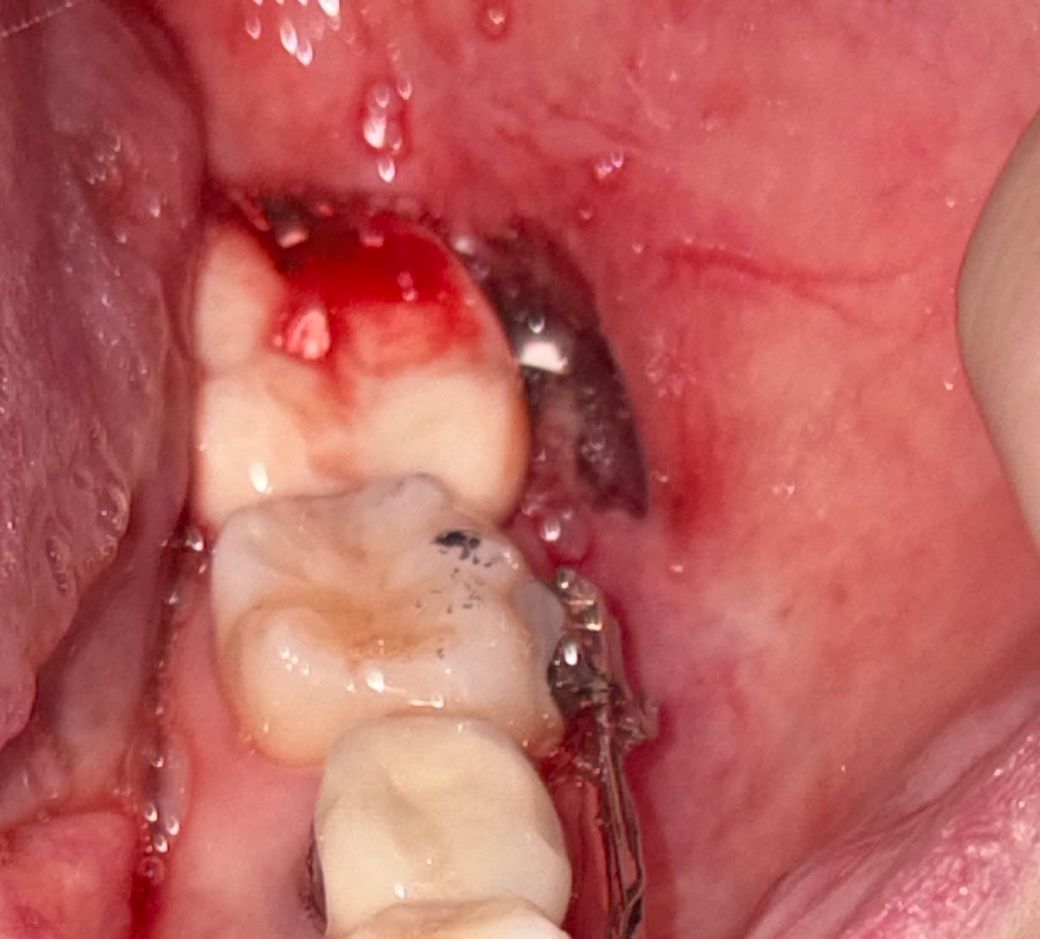

임시치아 씌우다가 볼이 베였는데 언제 아물까요..?

신경치료 중 입니다 어제 치과에서 임시치아 씌우기전에 맨 끝에 어금니를 기구로 가는 작업중에 볼이 깊게 베인거 같은데 안꼬매도 되나요? 아무는건 언제 아물까요..?

일반적으로 치과 기구(드릴)에 의한 깊지 않은 상처는 일주일 내로 회복됩니다. 지금 출혈이 지속되거나 불편감이 있는 경우 치과가서 조치를 취해달라고 하면 봉합해줄겁니다.